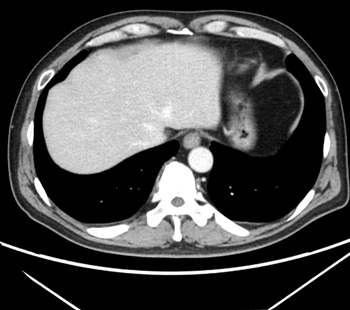

2025.1.16 CT

2025.4.9 CT

PI-PRADS 5 诊断,组织检查前治疗

20日集中 高频热疗 实施